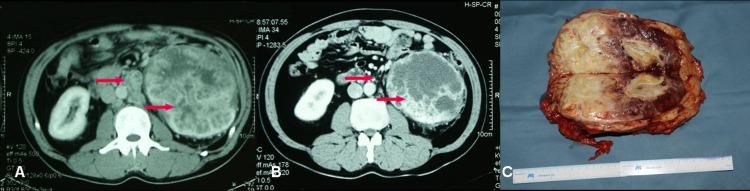

Among the 18 patients there were 13 male and 5 female, with a median age of 54.6 years. The objective response rate (ORR) of the operation on the selected patients is very high (94.4%), including 4 cases (22.2%) of partial response (PR) and 13 cases (72.2%) of stable disease (SD). After preoperative sorafenib treatment, the average tumor size of the 18 patients decreased from 7.8 cm (ranging from 3.6 to 19.2 cm) to 6.2 cm (ranging from 2.4 to 16.8 cm), and the median value of average tumor CT value decreased from 61HU to 52 HU. Among the 5 patients who had IVC tumor thrombi, the grades of tumor thrombi in 2 patients who were grade II before sorafenib treatment became grade I and grade 0 respectively, 2 patients of grade III both became grade II.

Preoperative neoadjuvant therapy with sorafenib for high risk RCC patients can significantly decrease primary tumor volume as well as tumor thrombus, which could help the nephron-sparing surgery (NSS) or radical nephrectomy to be done successfully.